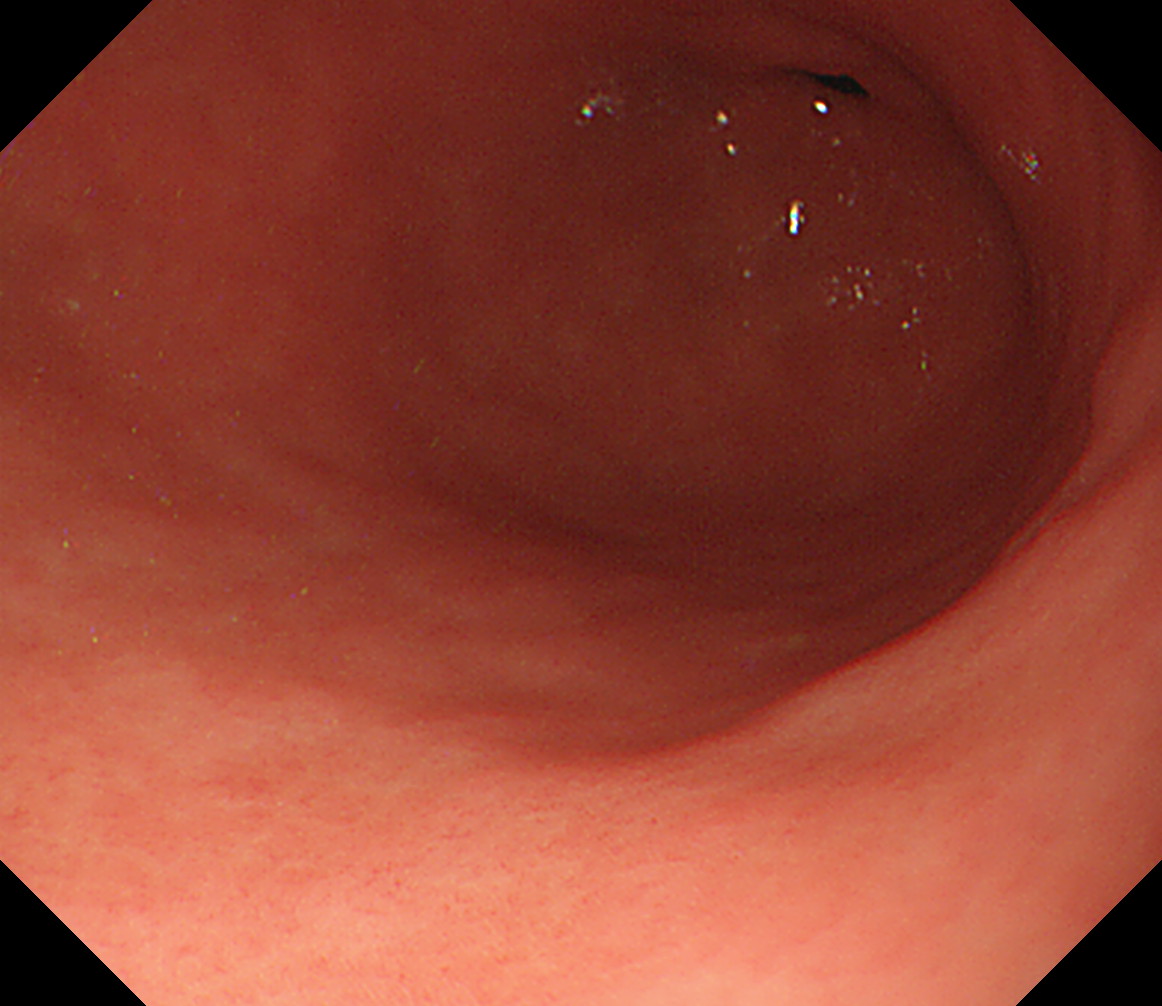

4 幽門部後壁 後壁から始めて反時計回りです 幽門部後壁

5 幽門部小弯 幽門部小弯

6 幽門部前壁 幽門部前壁

7 幽門部大弯 幽門部大弯